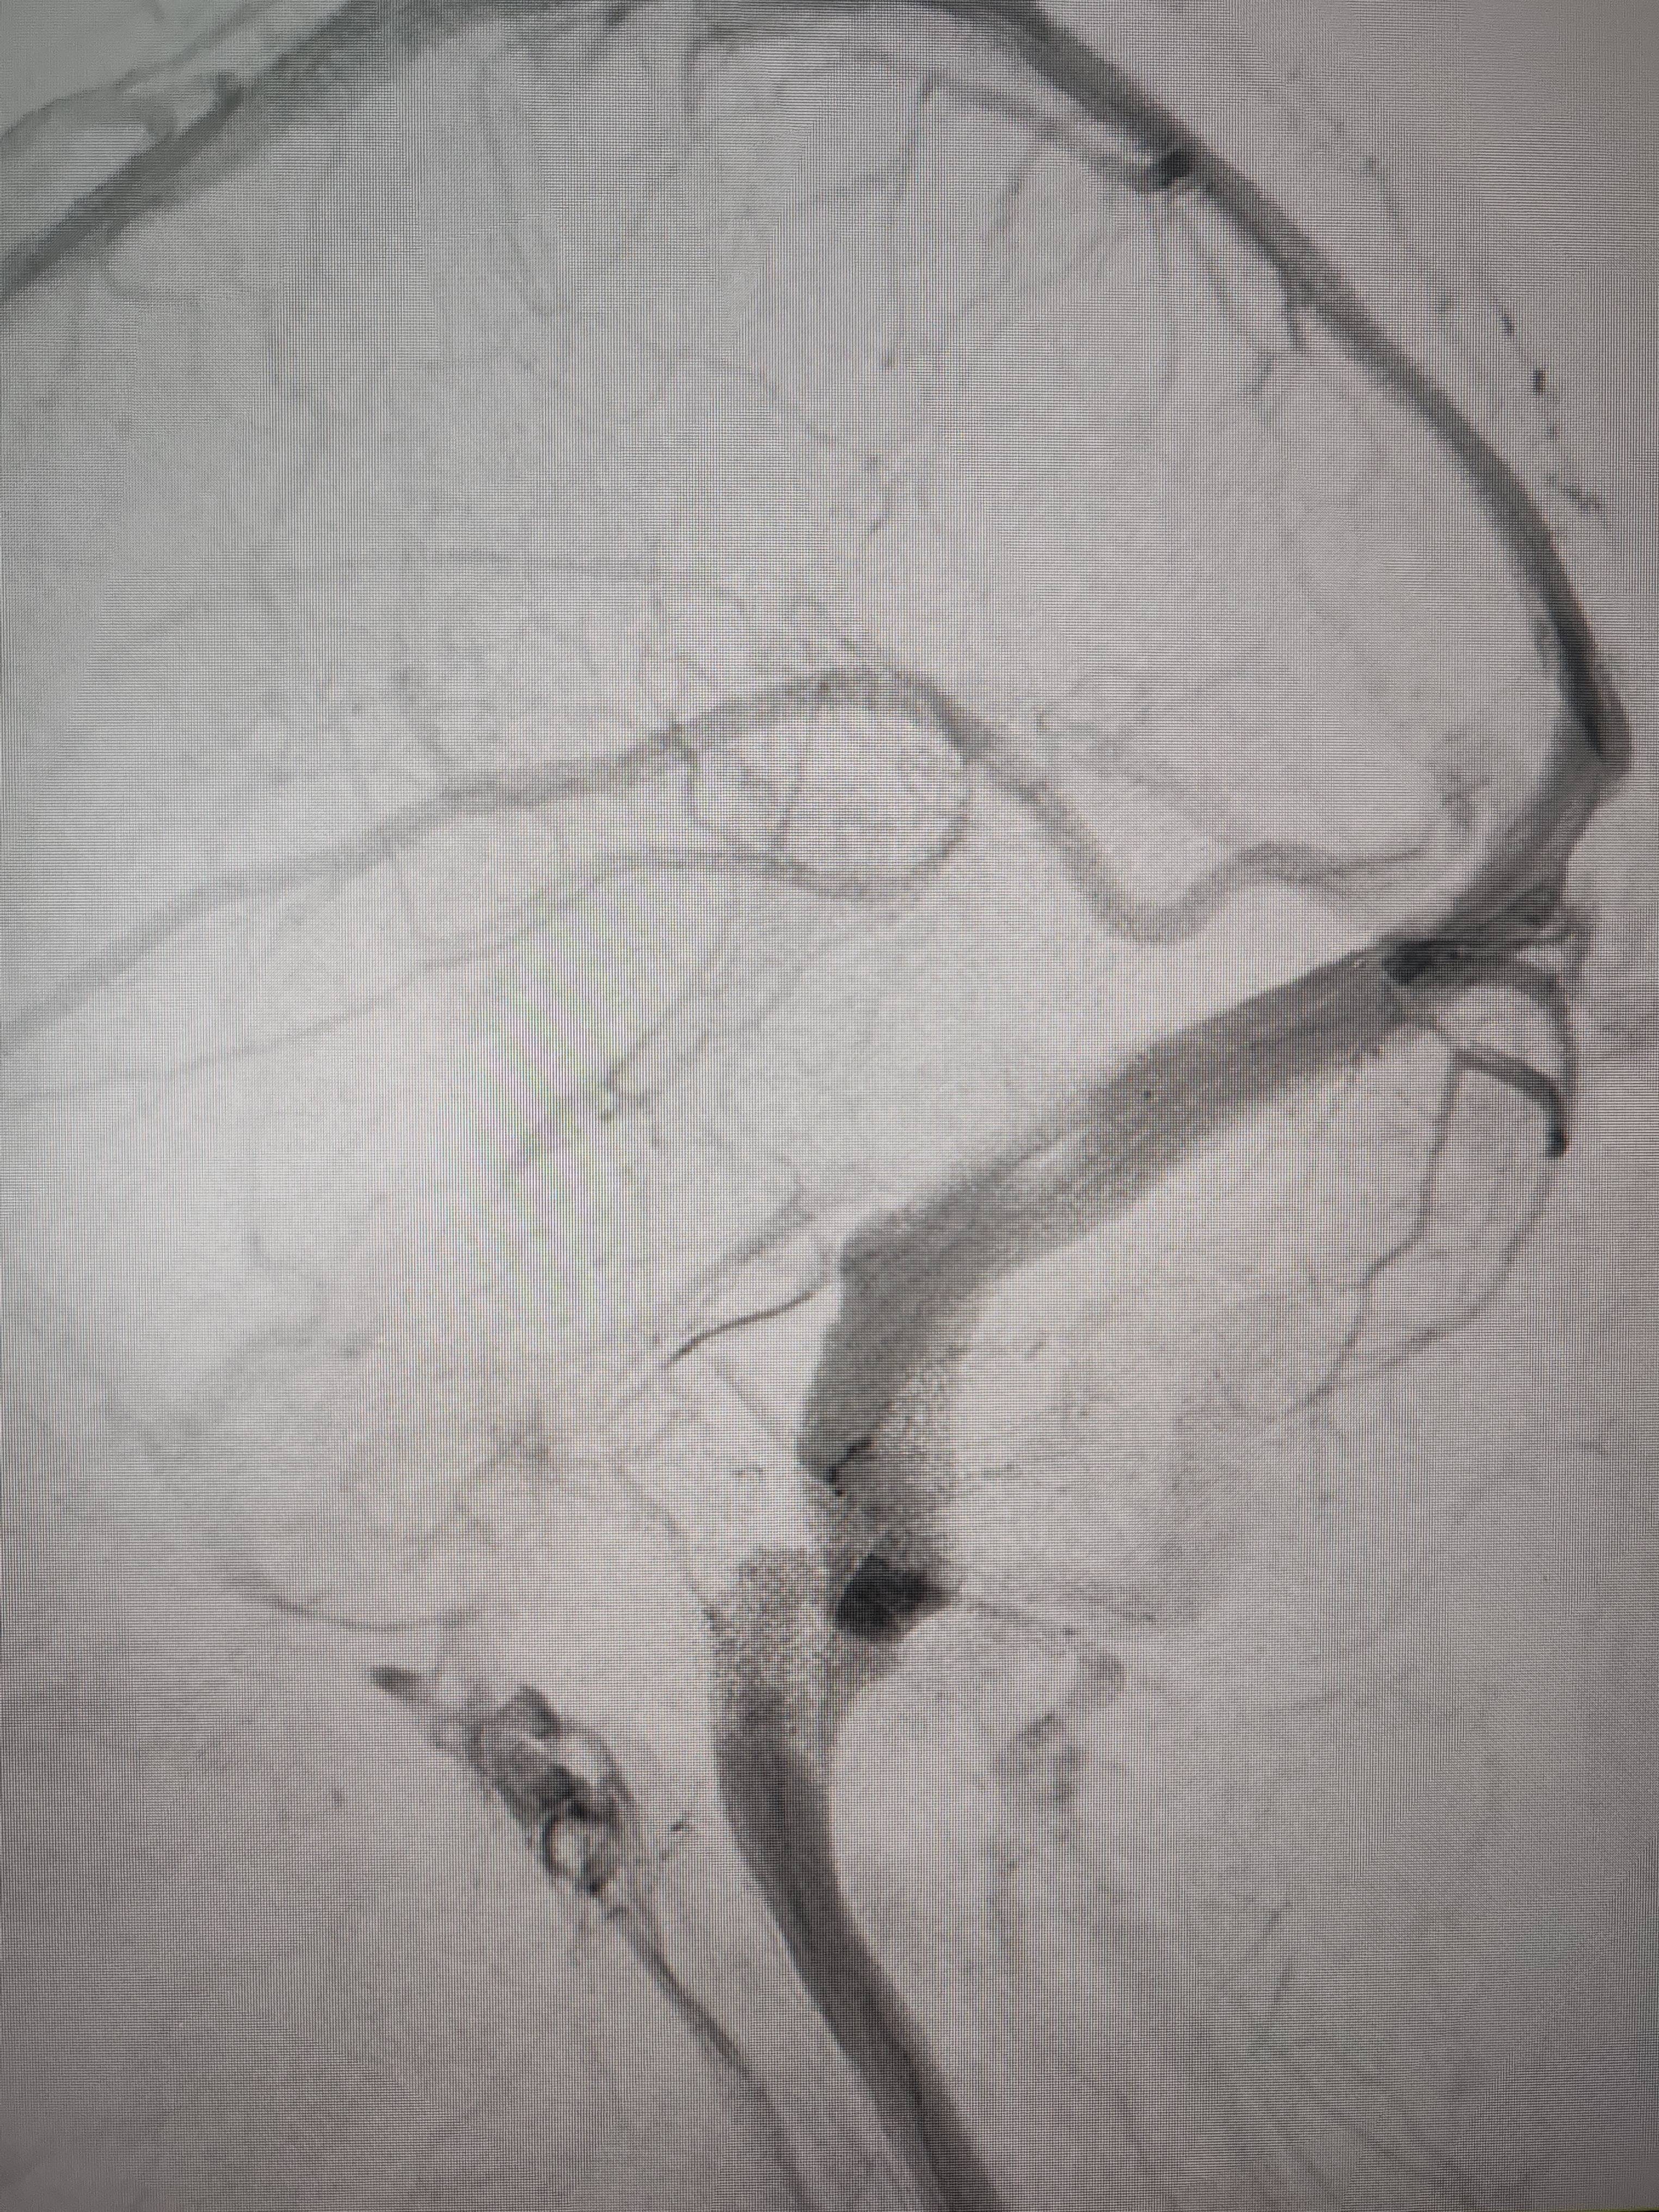

经过静脉窦支架置入手术治疗后,患者的静脉窦“堵点”被打通p2p理财雷。 南方+ 欧阳少伟 拍摄